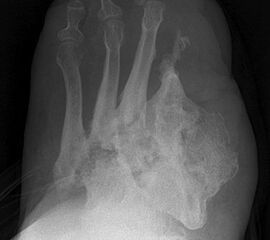

Amputationen an den Kleinzehenstrahlen

Amputation innerhalb der Kleinzehe

Eitrig-infiziertes Ulkus an der Spitze der 2. Zehe als Indikation zur Endgliedamputation.

Abbildung 13

Indikationen:

Chronisches Ulkus mit Infektion (Abb. 13).